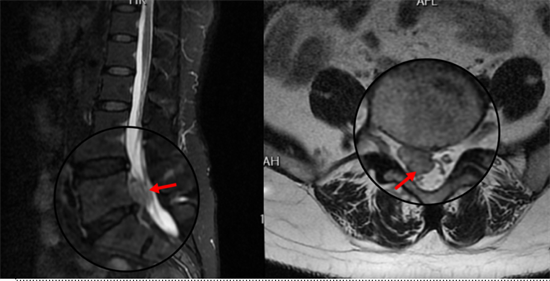

術(shù)前影像資料顯示L5/S1巨大脫出椎間盤(pán)并向近端高度游離

患者陽(yáng)某某,女,50歲,因反復(fù)腰部疼痛7年加重,并右下肢疼痛麻木半月到衡南縣人民醫(yī)院就診。骨科二區(qū)主任陳軾接診了患者,門診MRI檢查發(fā)現(xiàn)陽(yáng)女士為典型L5/S1巨大椎間盤(pán)脫出并壓迫神經(jīng)根,保守治療無(wú)效,建議手術(shù)治療。苗驚雷教授與縣醫(yī)院骨科二區(qū)專家團(tuán)隊(duì)為陽(yáng)女士量身定制了無(wú)需內(nèi)固定、創(chuàng)傷更小的UBE微創(chuàng)手術(shù)方案。術(shù)中通過(guò)兩個(gè)7mm的切口,精準(zhǔn)摘除脫出髓核,徹底解除神經(jīng)壓迫。術(shù)后次日,陽(yáng)女士下肢癥狀顯著緩解,已可自主下床活動(dòng)。

術(shù)后復(fù)查MRI顯示脫出椎間盤(pán)完全摘除,

神經(jīng)松解徹底,患者術(shù)后恢復(fù)良好